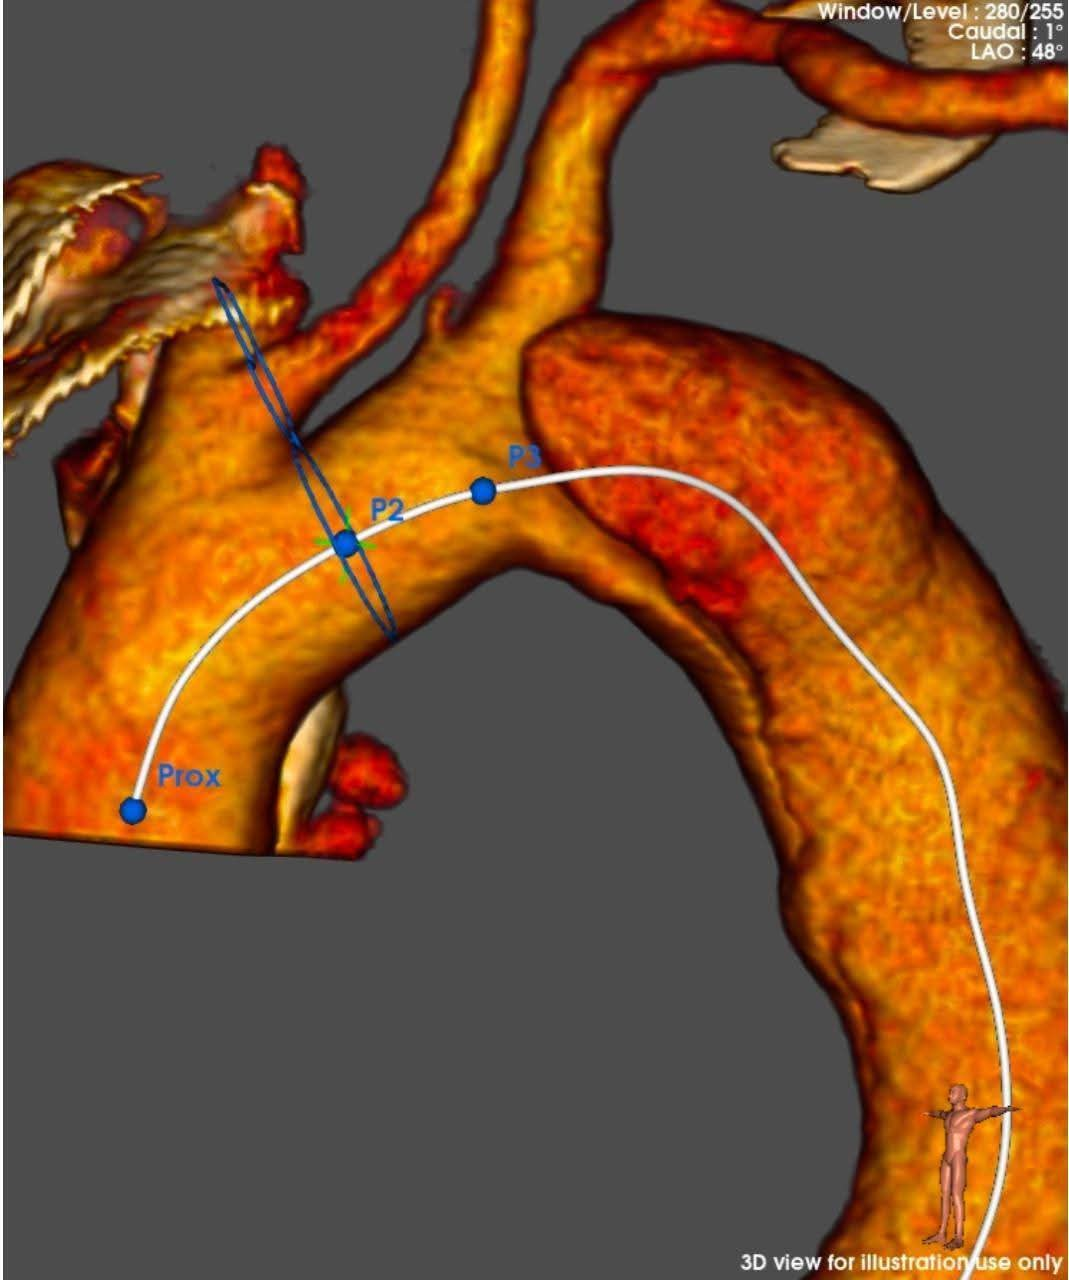

أجرى فريق أطباء قسم جراحة الأوعية الدموية بمستشفي مصر للطيران عملية إصلاح انشطار بالشريان الأورطي الصدري ممتد من الشريان تحت الترقوة الأيسر إلى شريان الحوض والفخذ الأيسر عن طريق استخدام الدعامات المغطاة Ankura™️ لتثبيت الشريان الأورطي الصدري واستعادة تدفق الدم الطبيعي.

وتم استخدام تقنية جديدة تحتاج الي مهارة ودقة عالية وللمرة الأولى في مستشفي مصر للطيران وهي عمل دعامة مغظاة فرعية لشريان الطرف العلوي الأيسر TEVAR + In situ fenestration for LSA + LSA stenting للحفاظ علي الدورة الدموية بالطرف العلوي الأيسر عن طريق عمل فتحة بالدعامة المغطاة بالشريان الأورطي الصدري باستخدام إبرة ( Futhrough™️ ) للحفاظ علي تدفق الدم بواسطة القسطرة التداخلية.